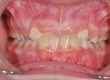

Клинични аспекти при прилагане на апарата Pendulum в смесено съзъбие

В тази статия си поставяме за цел да разискваме от клинична гледна точка позитивите и негативите при ползване на апарата Pendulum в смесено съзъбие. Ще разгледаме становищата за работа с апарата в случаите, когато са включени временните молари като опорна зона. Ще дадем какви са според нас клиничните предпоставки и индикации за използването на Pendulum в смесено съзъбие. Ще разгледаме терапевтичния протокол на няколко клинични случая, решени с прилагането на този апарат. Натрупаният от нас опит показва, че независимо кои зъби са в опорната зона се получава дистализиране на горни молари, но има разлики в не са значителни и не се отразяват негативно на основния ефект от действието на апарата Pendulum. Затова препоръчваме неговото ползване във всяка възраст и дентиция.